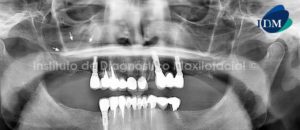

028 – Defecto de Stafne

Paciente 61 años de edad, sexo masculino, es referido a la consulta radiológica para la colocación de implantes dentales en el maxilar inferior.